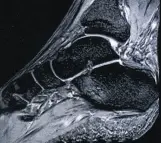

МРТ диагностика суставов, что дает расширенные возможности в установлении диагноза и в выборе тактики лечения.

Голеностопный сустав и стопа с сосудами